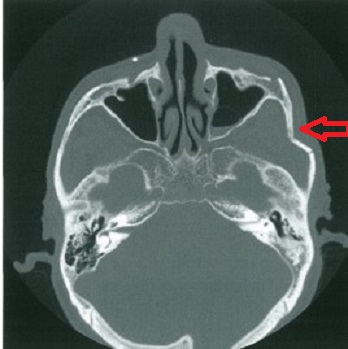

術前評価としての高分解能CTは必須です。

5:診 断

上記症状と X線撮影や CT が有効です。

特に 3D-CT が有益な場合が多いとされています。

診断にさいしてはX線のみに頼らず問診、視診、触診によって骨折部位を推定する習慣をつけておくことが大切です。